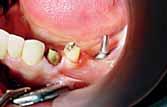

A 60 years old healthy female came into the clinic asking for a

fixed dental appliance to restore the bilateral edentulous posterior spaces of her own (Kennedy class 1).

There was a missing 6 and 7 on each side with compromised 4 and 5 on each.

The volume of available bone was insufficient to place a root form implant on the site of 7 (C-h available bone) a ridge mapping technique was used and a (C-w available bone) was also encountered.

The use of short implant in this case was not a treatment of choice; the crown - implant ratio is > 1.

A unilateral subperiosteal implant was suggested.

Surgery

First surgery

Infiltration was administered with long acting anesthetic (UbistesinTM forte 4%) to anesthetize the residual ridge posterior to the mental foramina from buccal and lingual sides and the lateral aspect of the ascending ramus.

An intraoral and extra oral scrub of the patient is performed with Chlorhexidine.5

Soft tissue reflection

Incision

The incision begins at the retro molar papilla at the base of the retro molar pad to the premolar.

A full thickness incision through the periosteum scores the underlying bone.

Reflections

A full thickness periosteal reflection exposes the underlying residual ridge and lateral regions of the mandible.

Evaluation of the crest

A knife edge ridge was exposed, thin knife like edges resorb shortly after implant insertion, if not before.5

An osteoplasty was performed to recontour the bone so the crest is broad enough to have a blood supply from the underlying trabecular bone. The osteoplasty was performed at the bone impression appointment. In this way the several weeks interval permit initial remodeling.